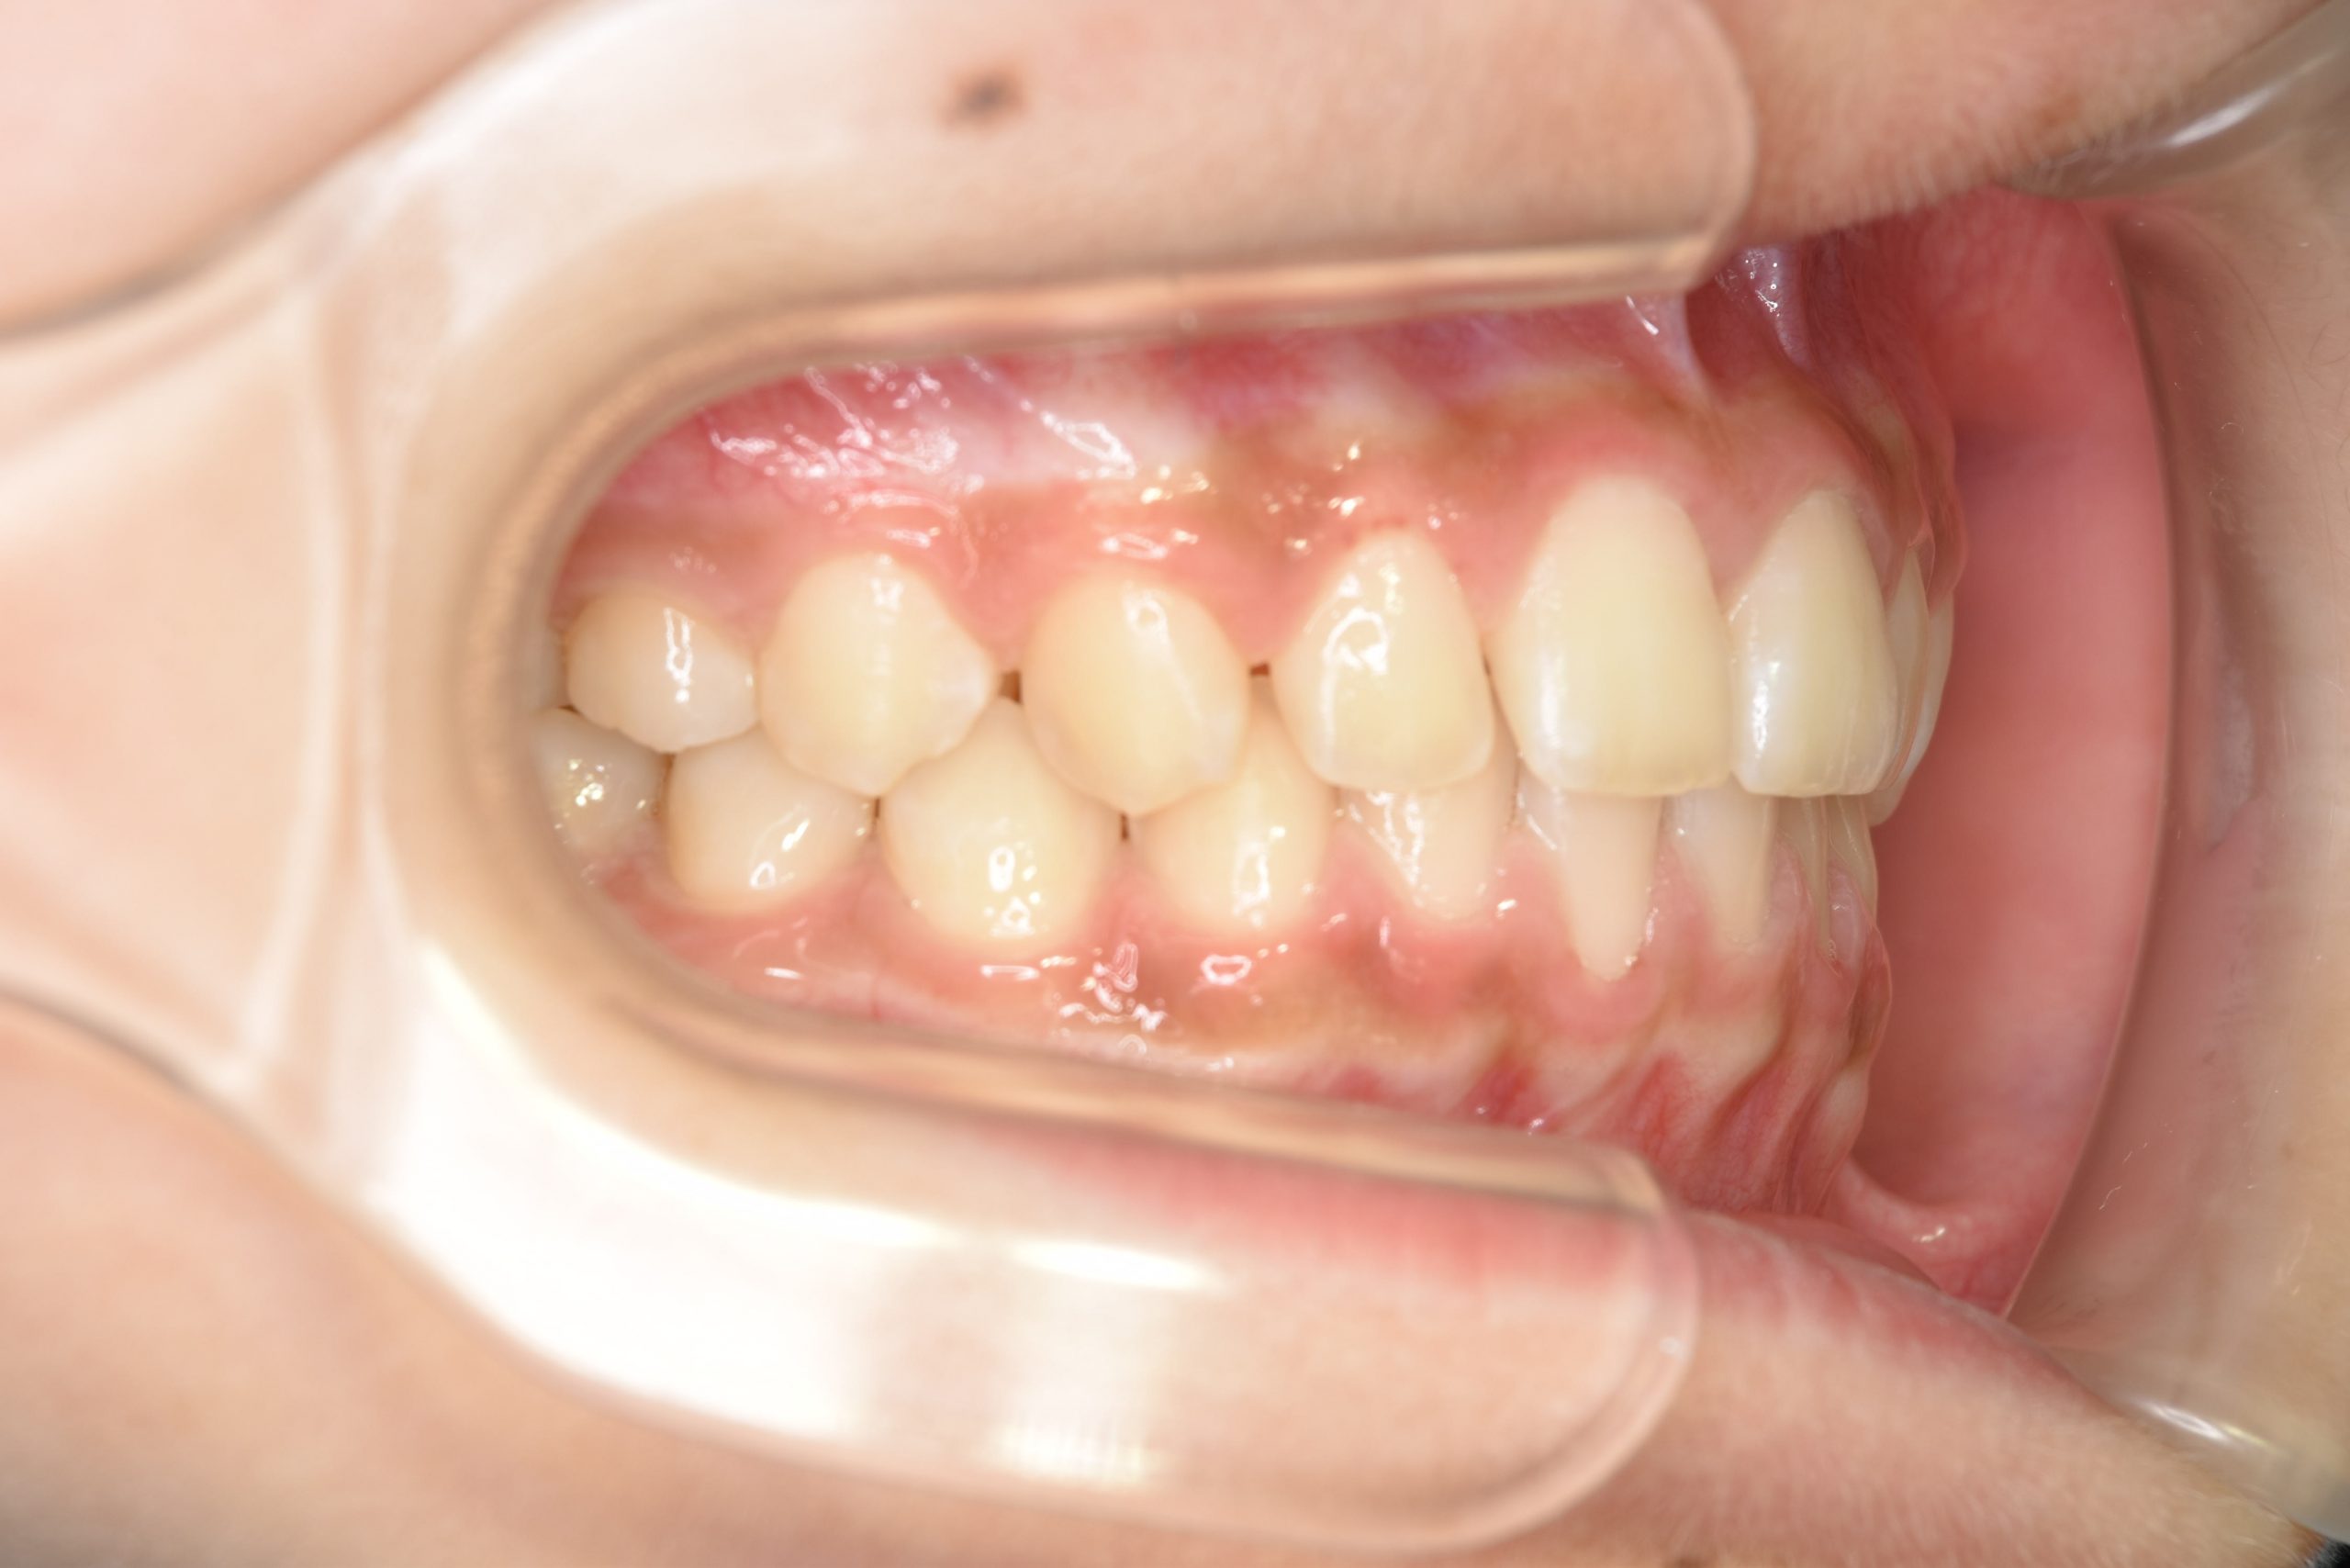

アフター

全顎ワイヤー矯正 症例_108

主訴 受け口|前歯がかみ合わない|顔貌

施術内容 小児矯正1期治療

治癒期間 3年11ヶ月間

費用 498,960円(税込)

リスク・副作用 違和感、不快感、痛み